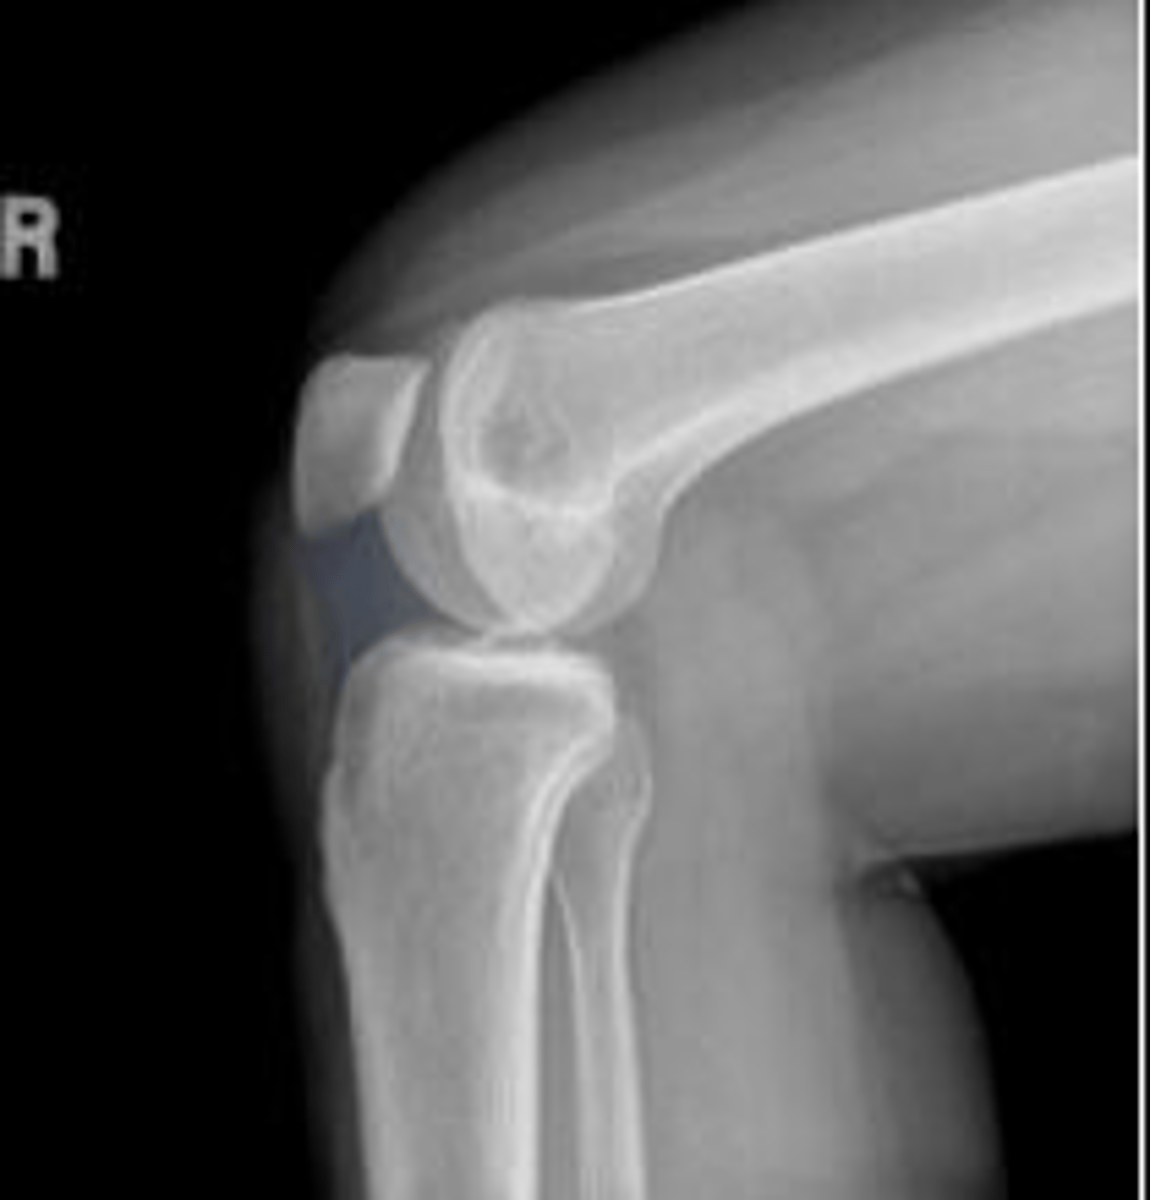

Right lateral knee

What is the name of the radiographic view?

Suprapatella pouch/recess/bursa of the left knee

What are the arrows pointing to?

Left patellar ligament

Left tibial tuberosity

Left suprapatellar fat pad

What is outlined?

Left prefemoral fat pad

Left patellofemoral joint space

What space are the arrows pointing to?

Left patella